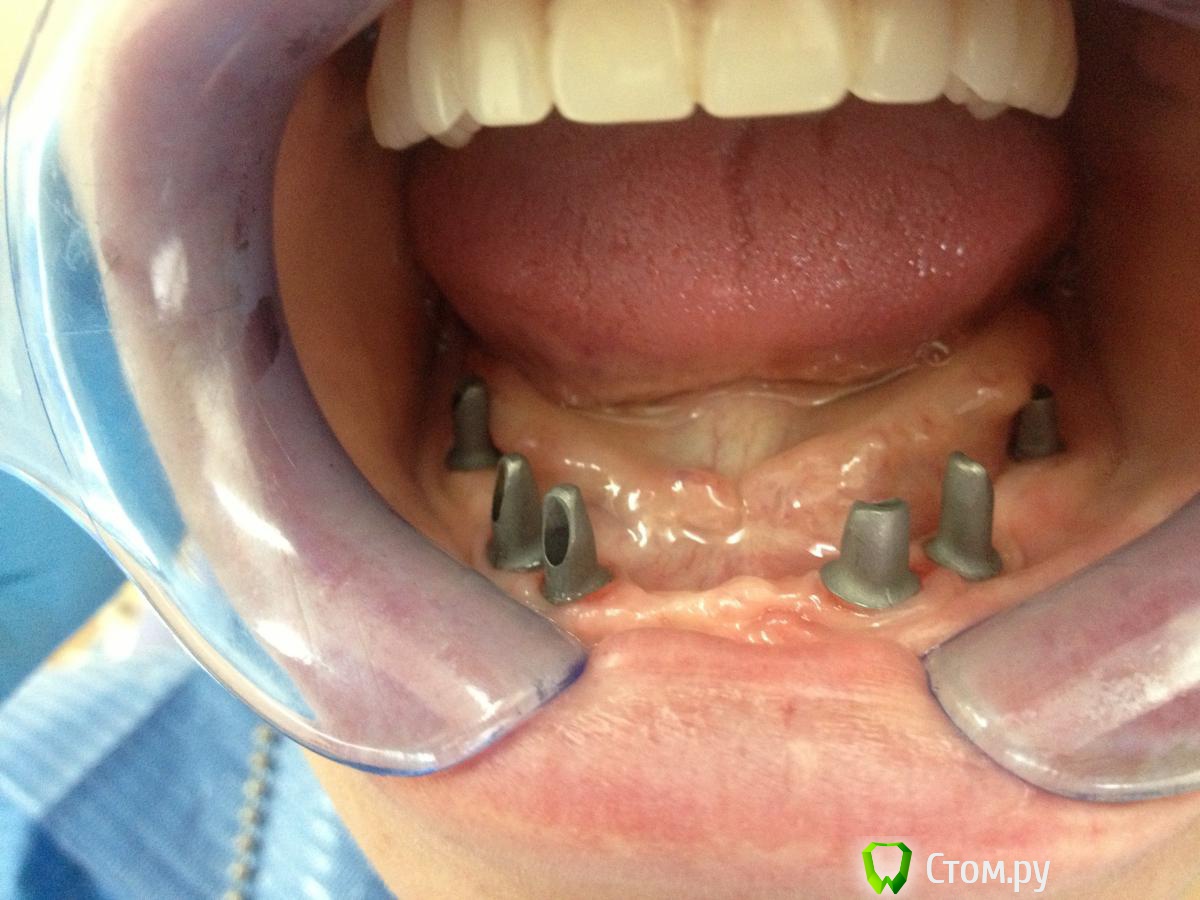

komar56 Опубликовано 15 февраля, 2014 Поделиться Опубликовано 15 февраля, 2014 Вроде все норм, во всяком случае в наших краях. Абатменты понравились! Ссылка на комментарий

MaxDok Опубликовано 15 февраля, 2014 Автор Поделиться Опубликовано 15 февраля, 2014 Вроде все норм, во всяком случае в наших краях. Абатменты понравились! Спасибо,вместе с техником сидел обрабатывал 2 Ссылка на комментарий

zubovolok Опубликовано 16 февраля, 2014 Поделиться Опубликовано 16 февраля, 2014 Спасибо! Цементная,ретракцию везде делал,суперфлоссы во все промежутки в момент цементировки.Каркас изготовлен по технологии лазерного спекания ,облицован керамикой .какая система имплантов использовалась? Дентиум? Можно по потробней про лазерное спекание? Ссылка на комментарий

MaxDok Опубликовано 17 февраля, 2014 Автор Поделиться Опубликовано 17 февраля, 2014 //// какая система имплантов использовалась? Дентиум? Можно по потробней про лазерное спекание?/// Она самая , что касается технологии изготовлении каркаса ..думаю я не отвечу подробнее чем google )) наберите в поисковике . Ссылка на комментарий